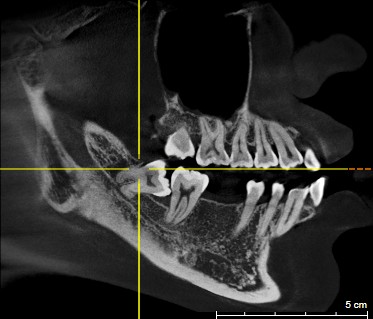

智齿位置、结构、生长形态各不相同,这也直接导致拔除的难易程度各不相等。一些长得比较"正"智齿,它的拔除过程相对比较轻松,且操作比较简单,耗材也较少,所以收费也就不会太高。但有一些智齿,它是倾斜长的,或者是水平长的,或者是埋在骨头里的,甚至压着神经管的,这种智齿拔除手术的难度和医生的操作要求都相对较高,因此价格也会相应地提升。